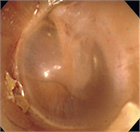

1. 上咽頭癌は日本では8割ほどがEpstein-Barr ウイルス(EBV)陽性の非角化型、残りはEBV陰性の角化型である。